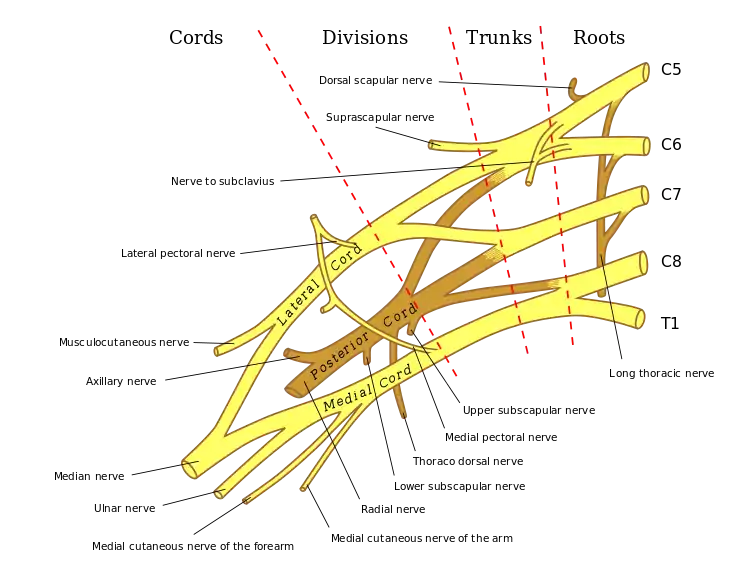

Structure

Arm

The ulnar nerve originates from the C8-T1 nerve roots (and occasionally carries C7 fibers which arise from the lateral cord),[4][5] which then form part of the medial cord of the brachial plexus, and descends medial to the brachial artery, up until the insertion point of coracobrachialis muscle (middle 5 cm over the medial border of the humerus). Then, it pierces the medial intermuscular septum and enters the posterior compartment of the arm, accompanied by superior ulnar collateral vessels. It runs at the posteromedial aspects of the humerus, passing behind the medial epicondyle (in the cubital tunnel) at the elbow, where it can be palpated by hand.[6]

Brachial plexus with courses of spinal nerves shown